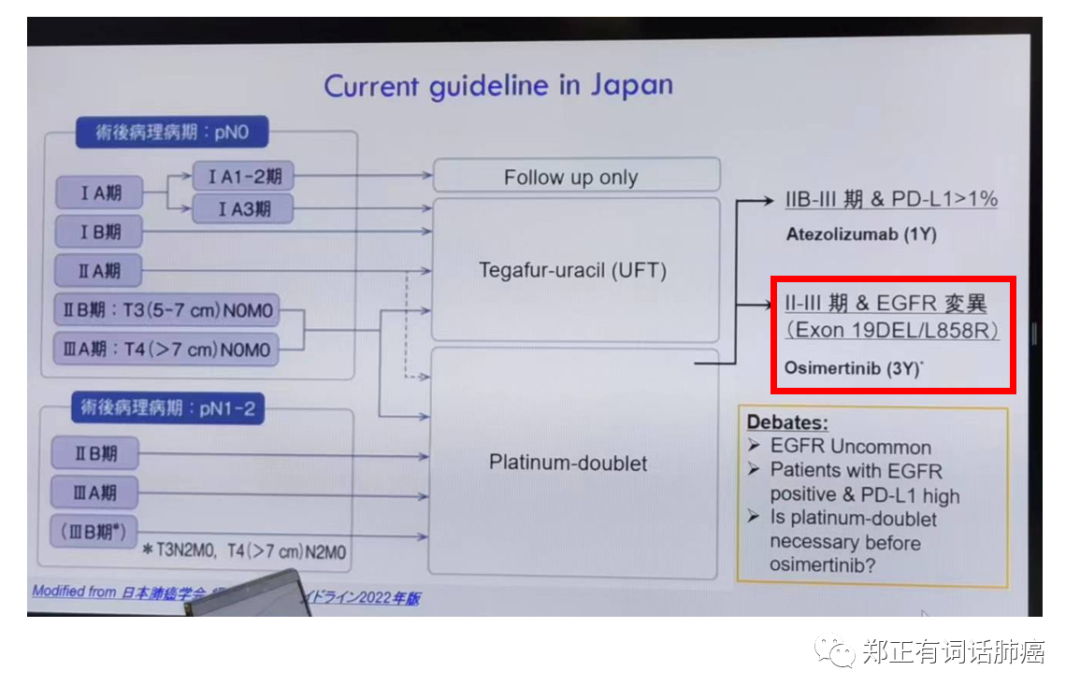

前段时间我受邀参加一个中日肺癌学术交流会,会上有一个日本专家跟我分享了日本肺癌诊疗现状,今天刚好也跟大家分享一下。

从图中可以看到,在日本,术后辅助靶向治疗主要在II期及以后应用,主要方案是服用奥西替尼3年。

由此我们可以反推,该研究在I期的研究结果或许才能更好地反映EGFR突变对肺癌生物学行为的影响。

I期高侵袭性在日本的生存数据不好,背后是否有靶向干预太少的原因?